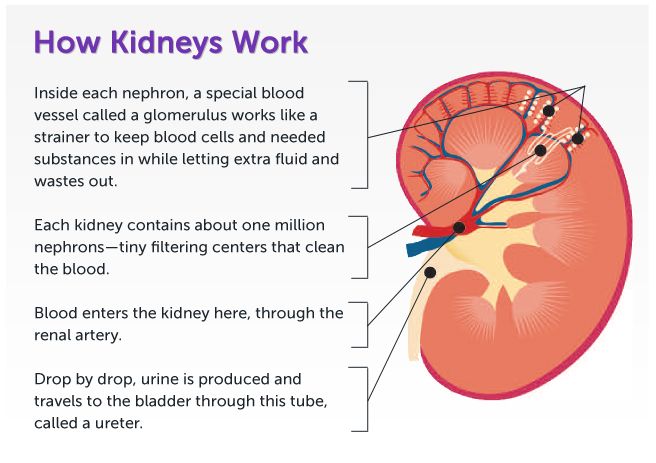

7. The Excretory System (human)

- Excretory organs and their functions e.g. kidney, skin and lungs.

- The process of excretion.

- Waste materials of excretion e.g. carbon (iv) oxide, sweat and urine.

- Need for excretion.